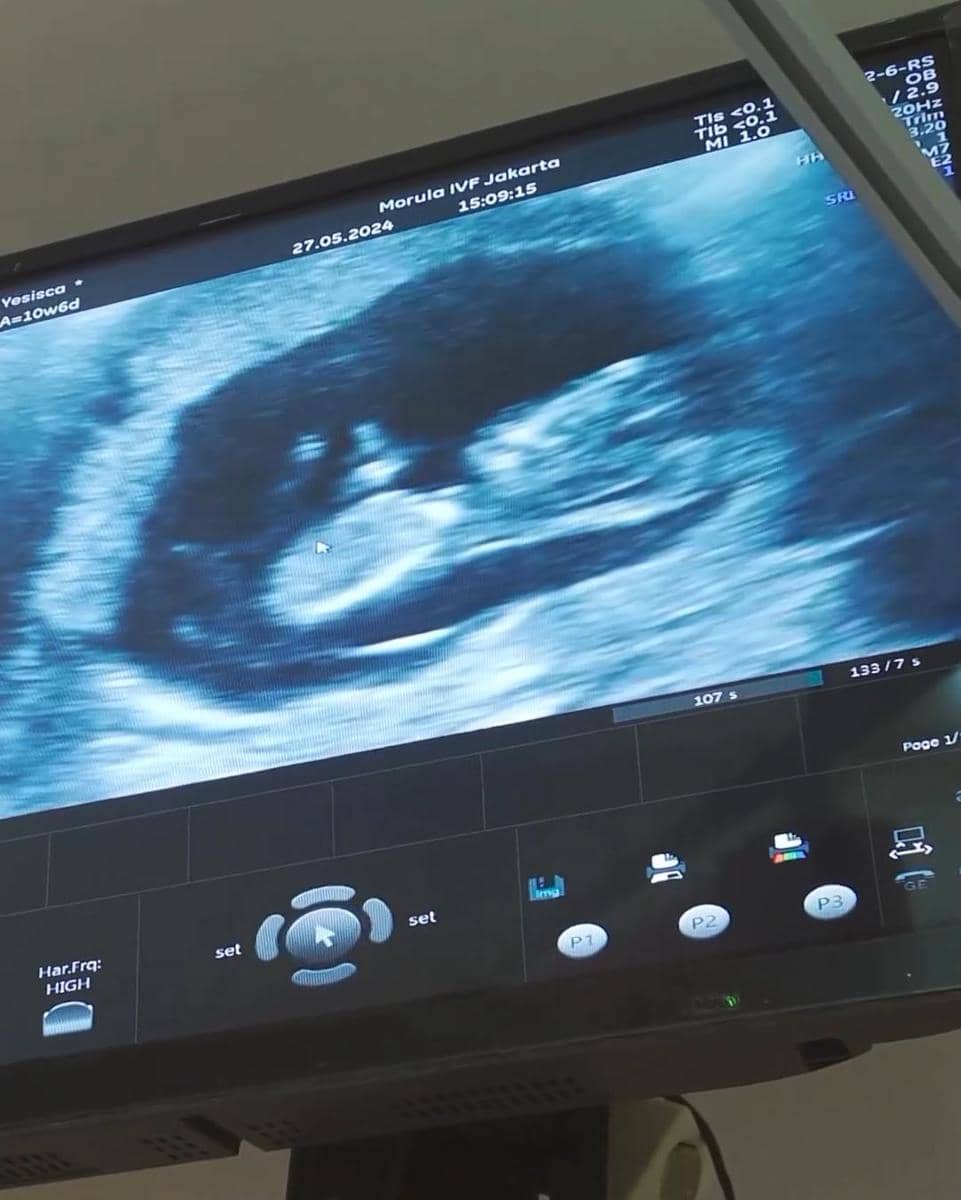

Pada Kamis (27/6/2024), Jedar membagikan video dirinya saat melakukan pemeriksaan USG bulanan. Terlihat perempuan kelahiran 1988 itu ditemani Vincent Verhaag dalam memantau perkembangan calon buat hati mereka.

Vincent tampak begitu bahagia ketika dokter memperlihatkan video janin di dalam kandungan istrinya. Dari hasil USG tersebut, terungkap bahwa usia kandungan Jedar sudah memasuki minggu ke-10.